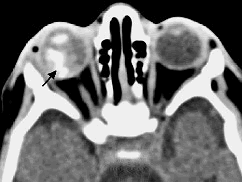

患者,女性,60岁,高血压病史20年。2小时前突发左眼视力丧失,自诉似“电灯开关关闭”。眼底检查。

(如图)最可能的诊断是()

-

最有特征的体征是()

该病的急诊处理原则是()